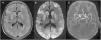

A 70-year-old woman with a history of chronic obstructive pulmonary disease, hypertension, and heart failure was transferred to our hospital after an episode of witnessed out-of-hospital cardiac arrest, for which she received 20min of cardiopulmonary resuscitation. At admission, she was comatose, requiring intubation. Neurological examination showed an absence of brainstem reflexes without any pharmacological influence. Twelve hours later, a magnetic resonance imaging (MRI) of the brain (Fig. 1) showed extensive bilateral, cortical–subcortical and basal ganglia hyperintensities on the fluid-attenuated inversion recovery sequence (A) with restricted diffusion (B) and normal arterial blood supply (C); findings consistent with hypoxic–ischemic brain injury (HIBI). The patient died 48h after admission. The current guidelines for HIBI suggest performing a brain MRI 2–5 days after the event, however recent data shows that the diffusion-weighted imaging (DWI) sequence on an MRI can predict neurological outcomes as early as 3h after this catastrophic event.